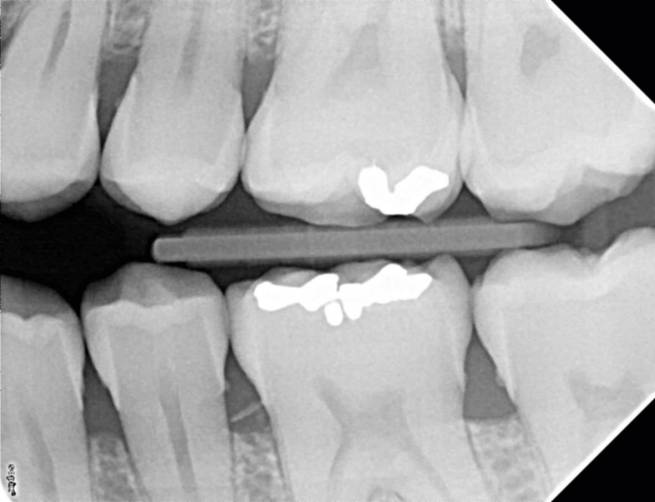

With the X-Mind® DC intraoral X-ray system, safe exposure levels and high quality images are guaranteed! Operating at high frequency, it facilitates the emission of very high quality radiation whenever it is used. This is made by the “double chamber” where the tube and the electronic components are separated. The control software automatically compensates for variations in main voltages and the radiation emitted is always of the highest quality to provide pictures with reproducible parameters.